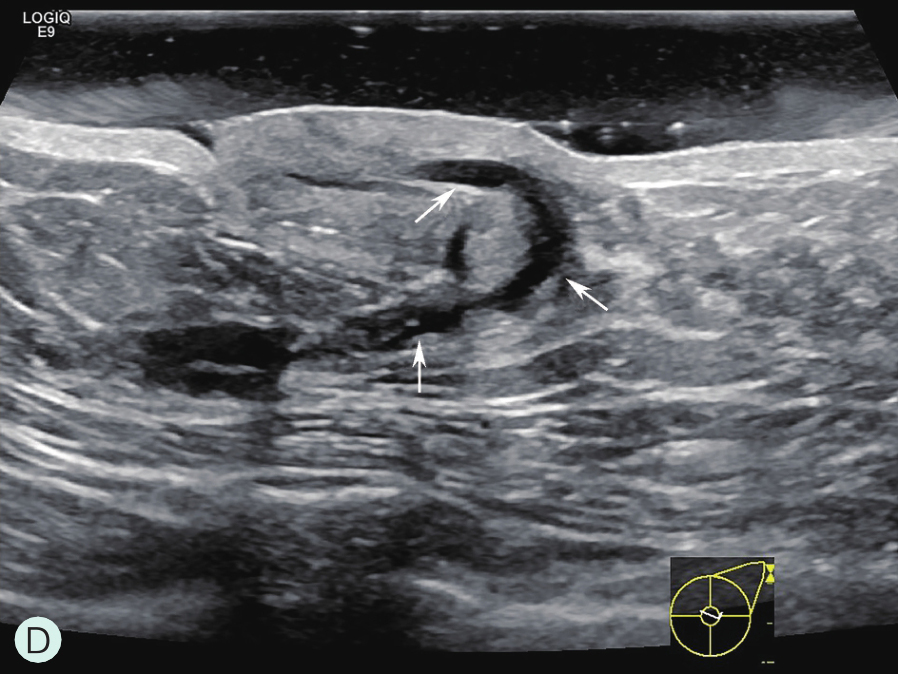

乳管系统为一由输乳管反复分支而呈现树状分支的结构单位,90%以上为2分支型,多分支型最多可达6分支,导管直径一般为2.0~4.5mm,随着导管分支逐渐变细。每个乳腺由15~20个腺小叶导管系统构成(图1-2-1A、图1-2-1B),每个系统组成一个乳腺叶,每个腺叶有其相应的导管系统,每个腺叶以乳头为中心呈轮辐样放射排列,各有一个导管向乳头引流,称输乳管(图1-2-1A),在乳头的基底部,距乳头开口约0.5cm处呈壶腹样膨大(图1-2-1C~图1-2-1E),口径为5~6mm,充满乳汁直径可达6~8mm,供暂时储存乳汁,该膨大区称乳窦。窦外末段输入管口径又缩小,并开口于乳头。从乳管开口到壶腹部的一段导管内衬以多层鳞状上皮细胞,以下的中小导管及腺泡内衬单层柱状细胞。若单个导管内的上皮细胞增殖呈乳头状突入管腔,称为导管内乳头状瘤。乳腺癌主要来源于腺管的柱状上皮细胞,发生于腺泡的癌仅占5%。

图1-2-1 乳腺结构与影像图

A.乳腺模式图;B.乳腺小叶声像图;C、D.乳腺导管声像图;E.乳腺扩张导管MRI图